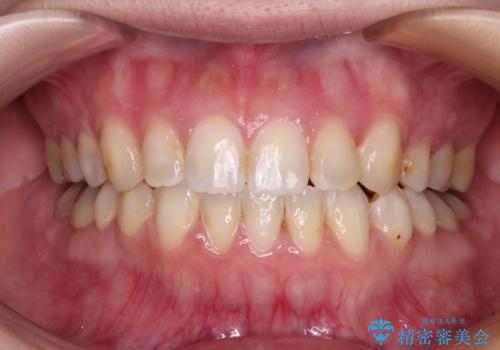

デコボコと口元の突出感を改善 抜歯矯正治療

- 八重歯を気にして来院された患者様です。

上下左右の犬歯が八重歯になっており、口元にもやや突出感があるため、上下左右の小臼歯4本を抜歯し、ワイヤー装置にて矯正治療を行うこととしました。